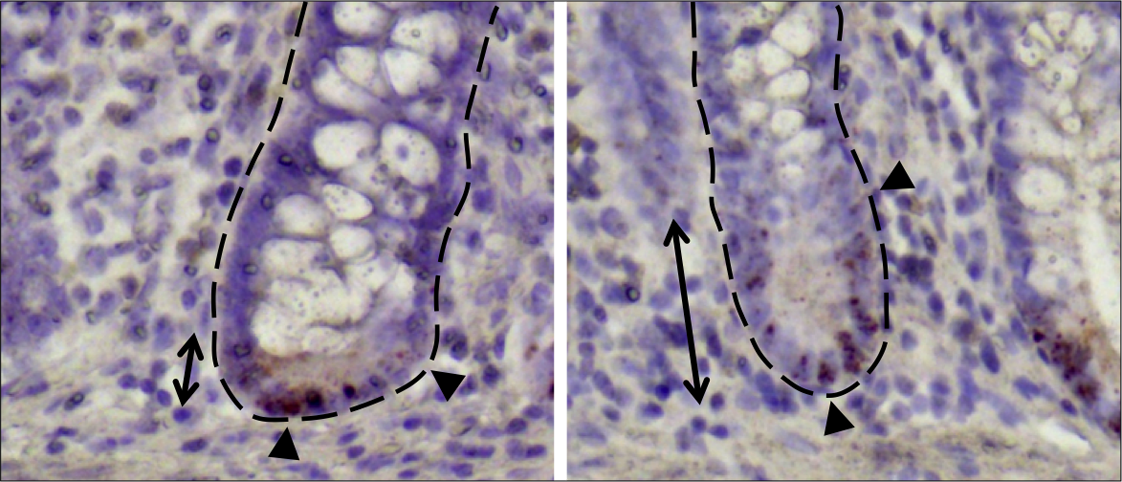

Stem cells are indispensable for the maintenance and regeneration of tissues. Intestinal stem cells inside the intestines are intermingled with so-called Paneth cells, which are responsible for the local immune defense and for creating an environment in which the stem cells can prosper, thus termed guardians of the stem cell niche.

Patients suffering from Crohn’s disease have fewer Paneth cells and furthermore, these are limited in their functionality. The research group examined the causes for alterations in Paneth cells and attempted to determine the importance of stem cell metabolism in this context.

The study showed that microscopic alterations in stem cell niche were particularly prevalent in those patients who showed symptoms of a relapse of inflammation after six months.

In both human patients and mouse models, alterations in Paneth and stem cells coincided with decreased mitochondria functionality.